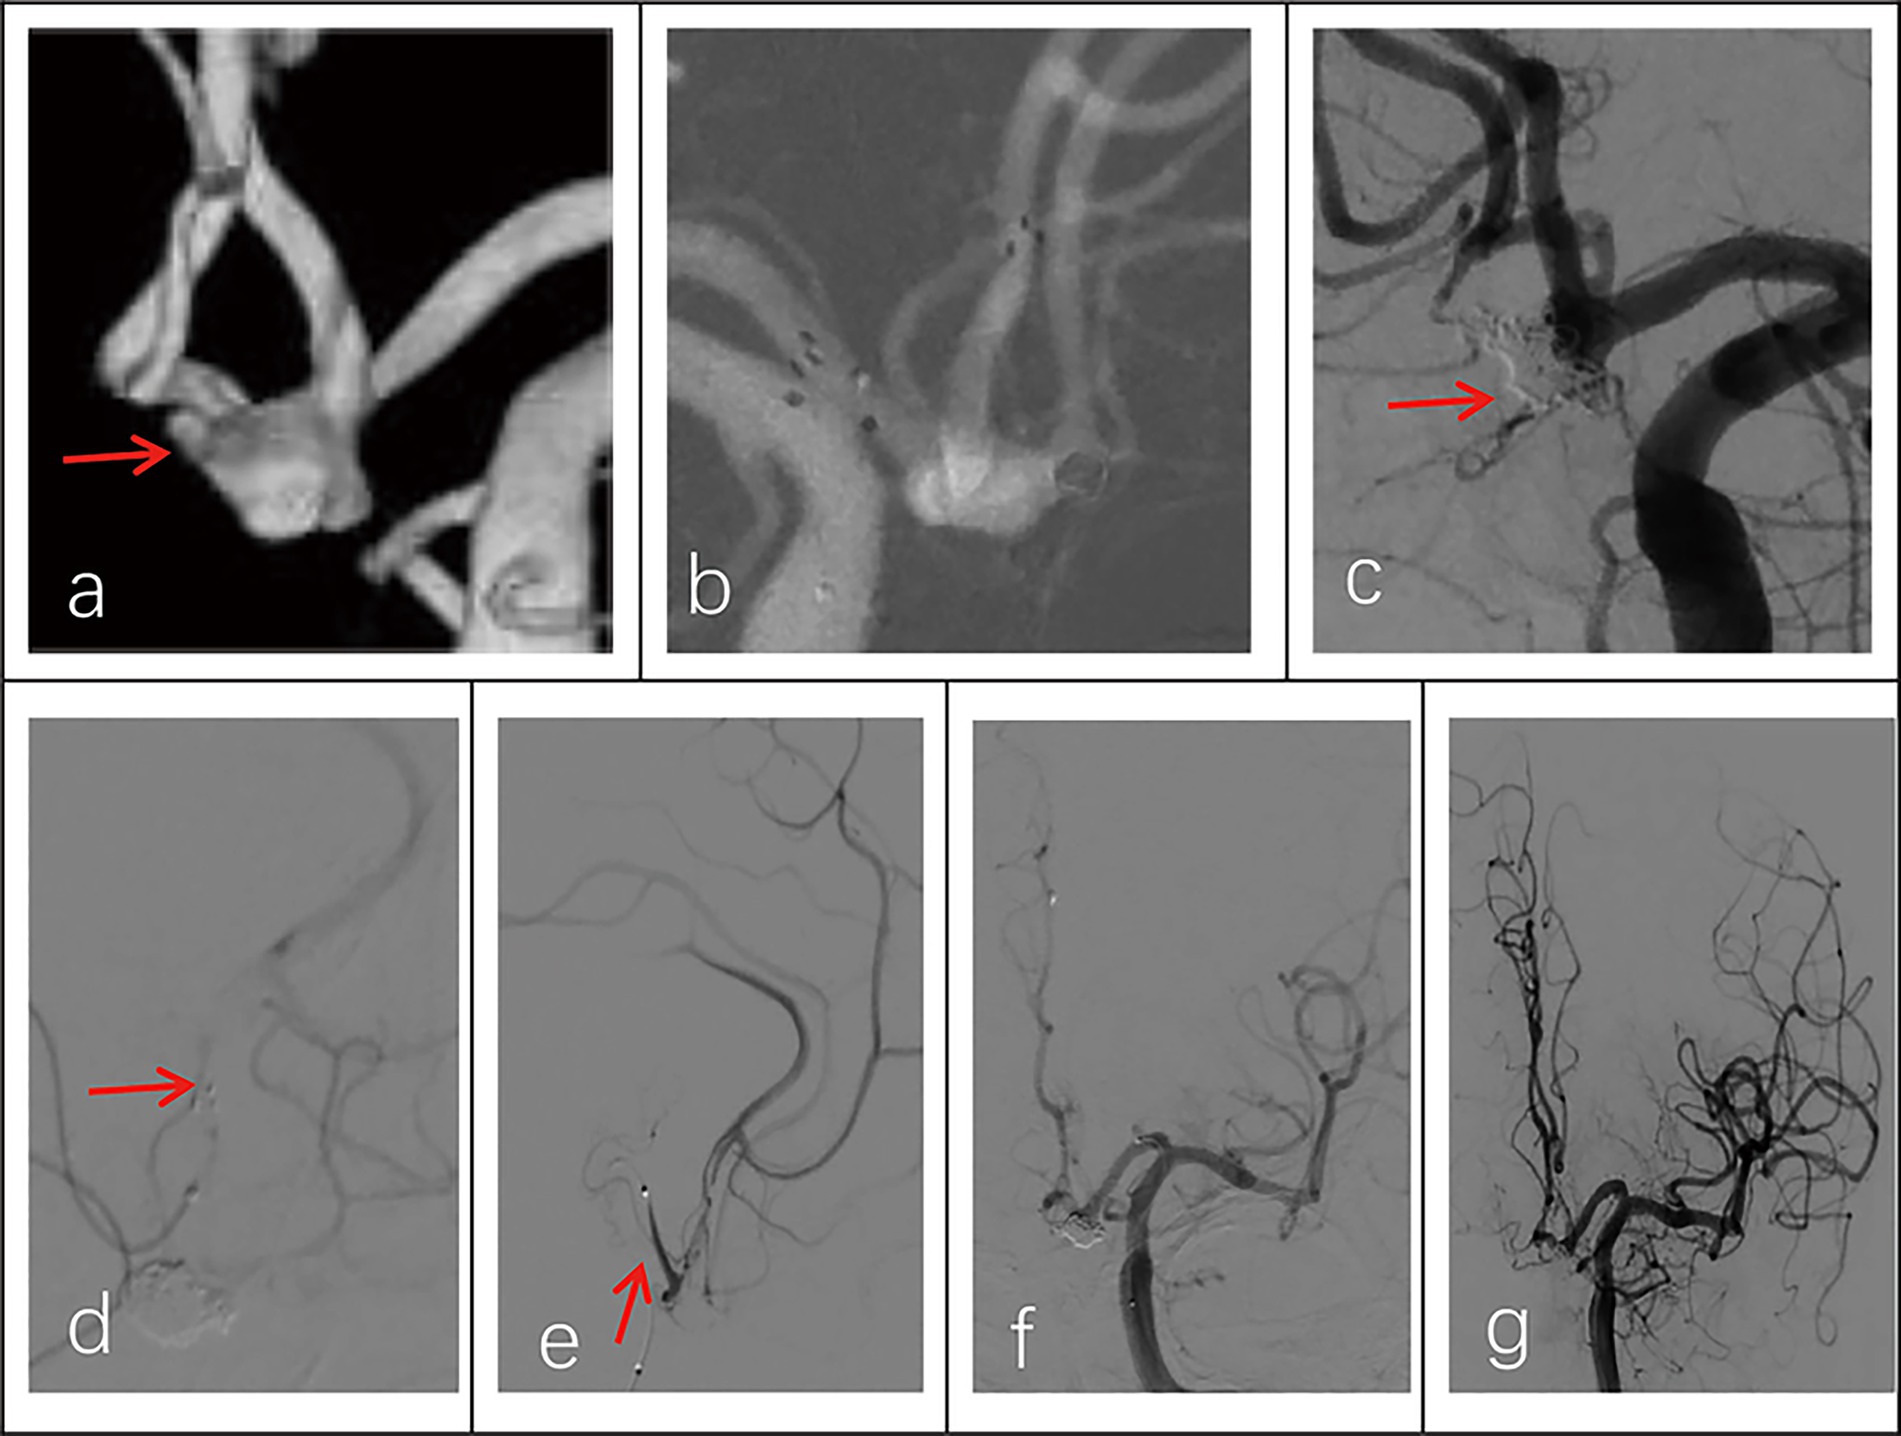

All 30 patients had effective Neuroform Atlas stent deployments, with good expansion and location. Twenty-three cases (76.7%) employed the double micro catheter approach, whereas 7 cases (23.3%) employed the single micro catheter technique. Immediate postprocedural angiography showed complete occlusion (RR Grade I) in 18 patients (94.7%) (Figure 1 shows the representative case), neck remnant (RR Grade II) in 0 (0%), and partial occlusion (RR Grade III) in 1 (5.3%). The data of the other 11 patients was unavailable because they refused to accept postprocedural angiography whose follow-up outcomes were good (mRS score ≤2). Clinical outcome was favorable in 29 patients (96.7%) and poor in 1 (3.3%). The mRS score was 3 in the single patient with poor clinical outcomes. Postprocedural angiographic and clinical outcomes are shown in Table 2 and Supplementary Figure 1. Procedure-related complications occurred in three patients (10%), including two cases of hemorrhagic complication and one case of thrombotic complication. No procedure-related death occurred. Contrast medium leakage was discovered during coil delivery in two patients with hemorrhagic complications, but it vanished during the angiography examination following rapid coil delivery. In terms of neurological recovery, mRS score was ≤2 (Figure 2 shows the representative case). One case was found post-procedural acute intrastent thrombosis. With slow injection of tirofiban hydrochloride (0.2 mL/kg) through the guiding catheter, angiography showed disappearance of thrombosis with effective reperfusion and neurological recovery, that was, mRS score ≤2. Postprocedural CT scan showed all patients had satisfactory embolization before smooth discharge from the hospital (Figure 3).

Figure 2. Imaging data of a 44-year-old female patient with a ruptured wide-necked anterior communicating artery (ACoA) aneurysm. (a) Location of a ruptured wide-necked ACoA aneurysm (red line). (b) The stent was successfully deployed from the ipsilateral A2 to the A1 segment. (c) The microcatheter was delivered into the aneurysm sac to place the coils. (d) The shape of coil embolization was different from 3D reconstruction of the aneurysm. The aneurysm was packed with more coils until aneurysm partial occlusion (modified Raymond-Roy Class II). Contrast medium leakage from the aneurysm sac (red arrowhead) suggests aneurysm rupture and hemorrhage. (e) Following continued rapid coil packing, subsequent angiography revealed no contrast medium leakage from the aneurysm (red arrowhead). (f) Follow-up angiography at 6 months showed complete occlusion (modified Raymond-Roy Class I) of the aneurysm (red arrowhead), with no visualization of the aneurysm sac or neck.